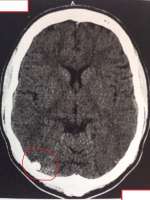

Делал КТ головы, нашли маленькую менингиому.

По сути я как понял это доробкачетвенная опухоль головного мозга.

Не могу найти статью в расписании болезней применимой к этой менингеоме. там либо злокачетсвенная, либо доброкачесвенная но не мозга.

Надо закосить от армейки.

>>555029

А что невролог-то говорит? Раз уже опухоль нашли, то должны разобраться.

ходил к нейрохирургу на днях показывал снимки (полугодовалой давности), направил на дополнительное КТ, но это уже после нового года.

Может МРТ сделать? КТ опухоли головы не очень хорошо видит.

>это доробкачетвенная опухоль

А если она на четверть сдавит твой мозг? Рекомендовали динамическое наблюдение?

Аноним 31/12/16 Суб 13:56:32  555116

Ну если на четверть сдавит, то пизда наверное.

Аноним 31/12/16 Суб 14:37:03  555125

>>555116

Она склонна увеличиваться. Доброкачественные опухоли мозга на самом деле очень коварны и опасны.

Ну, буду следить динамику. Врач сказал эта хуйня почти окостенела уже, (имеет сходную плотность с костью)

>>555129

Ты головой никогда не ударялся сильно?

Аноним 31/12/16 Суб 15:36:14  555136

>>555134

Много раз сотряс получал.

После последнего сотряса невролог отправила на КТ и там это обнаружилось.

Сколько времени эта хрень там сидит не знаю, так как до этого жил в лютом мухосранске, и никогда не проверялся.

Аноним 31/12/16 Суб 16:03:46  555145

>>555137

Я в нейрохирургии не шарю, но может это вообще старая оссифицированная гематома.

Можешь не переживать, плотность такая же, как и у кости, так что все норм

Но хорошо бы сделать МРТ с разными усилениями, тогда можно будет почти точно успокоиться